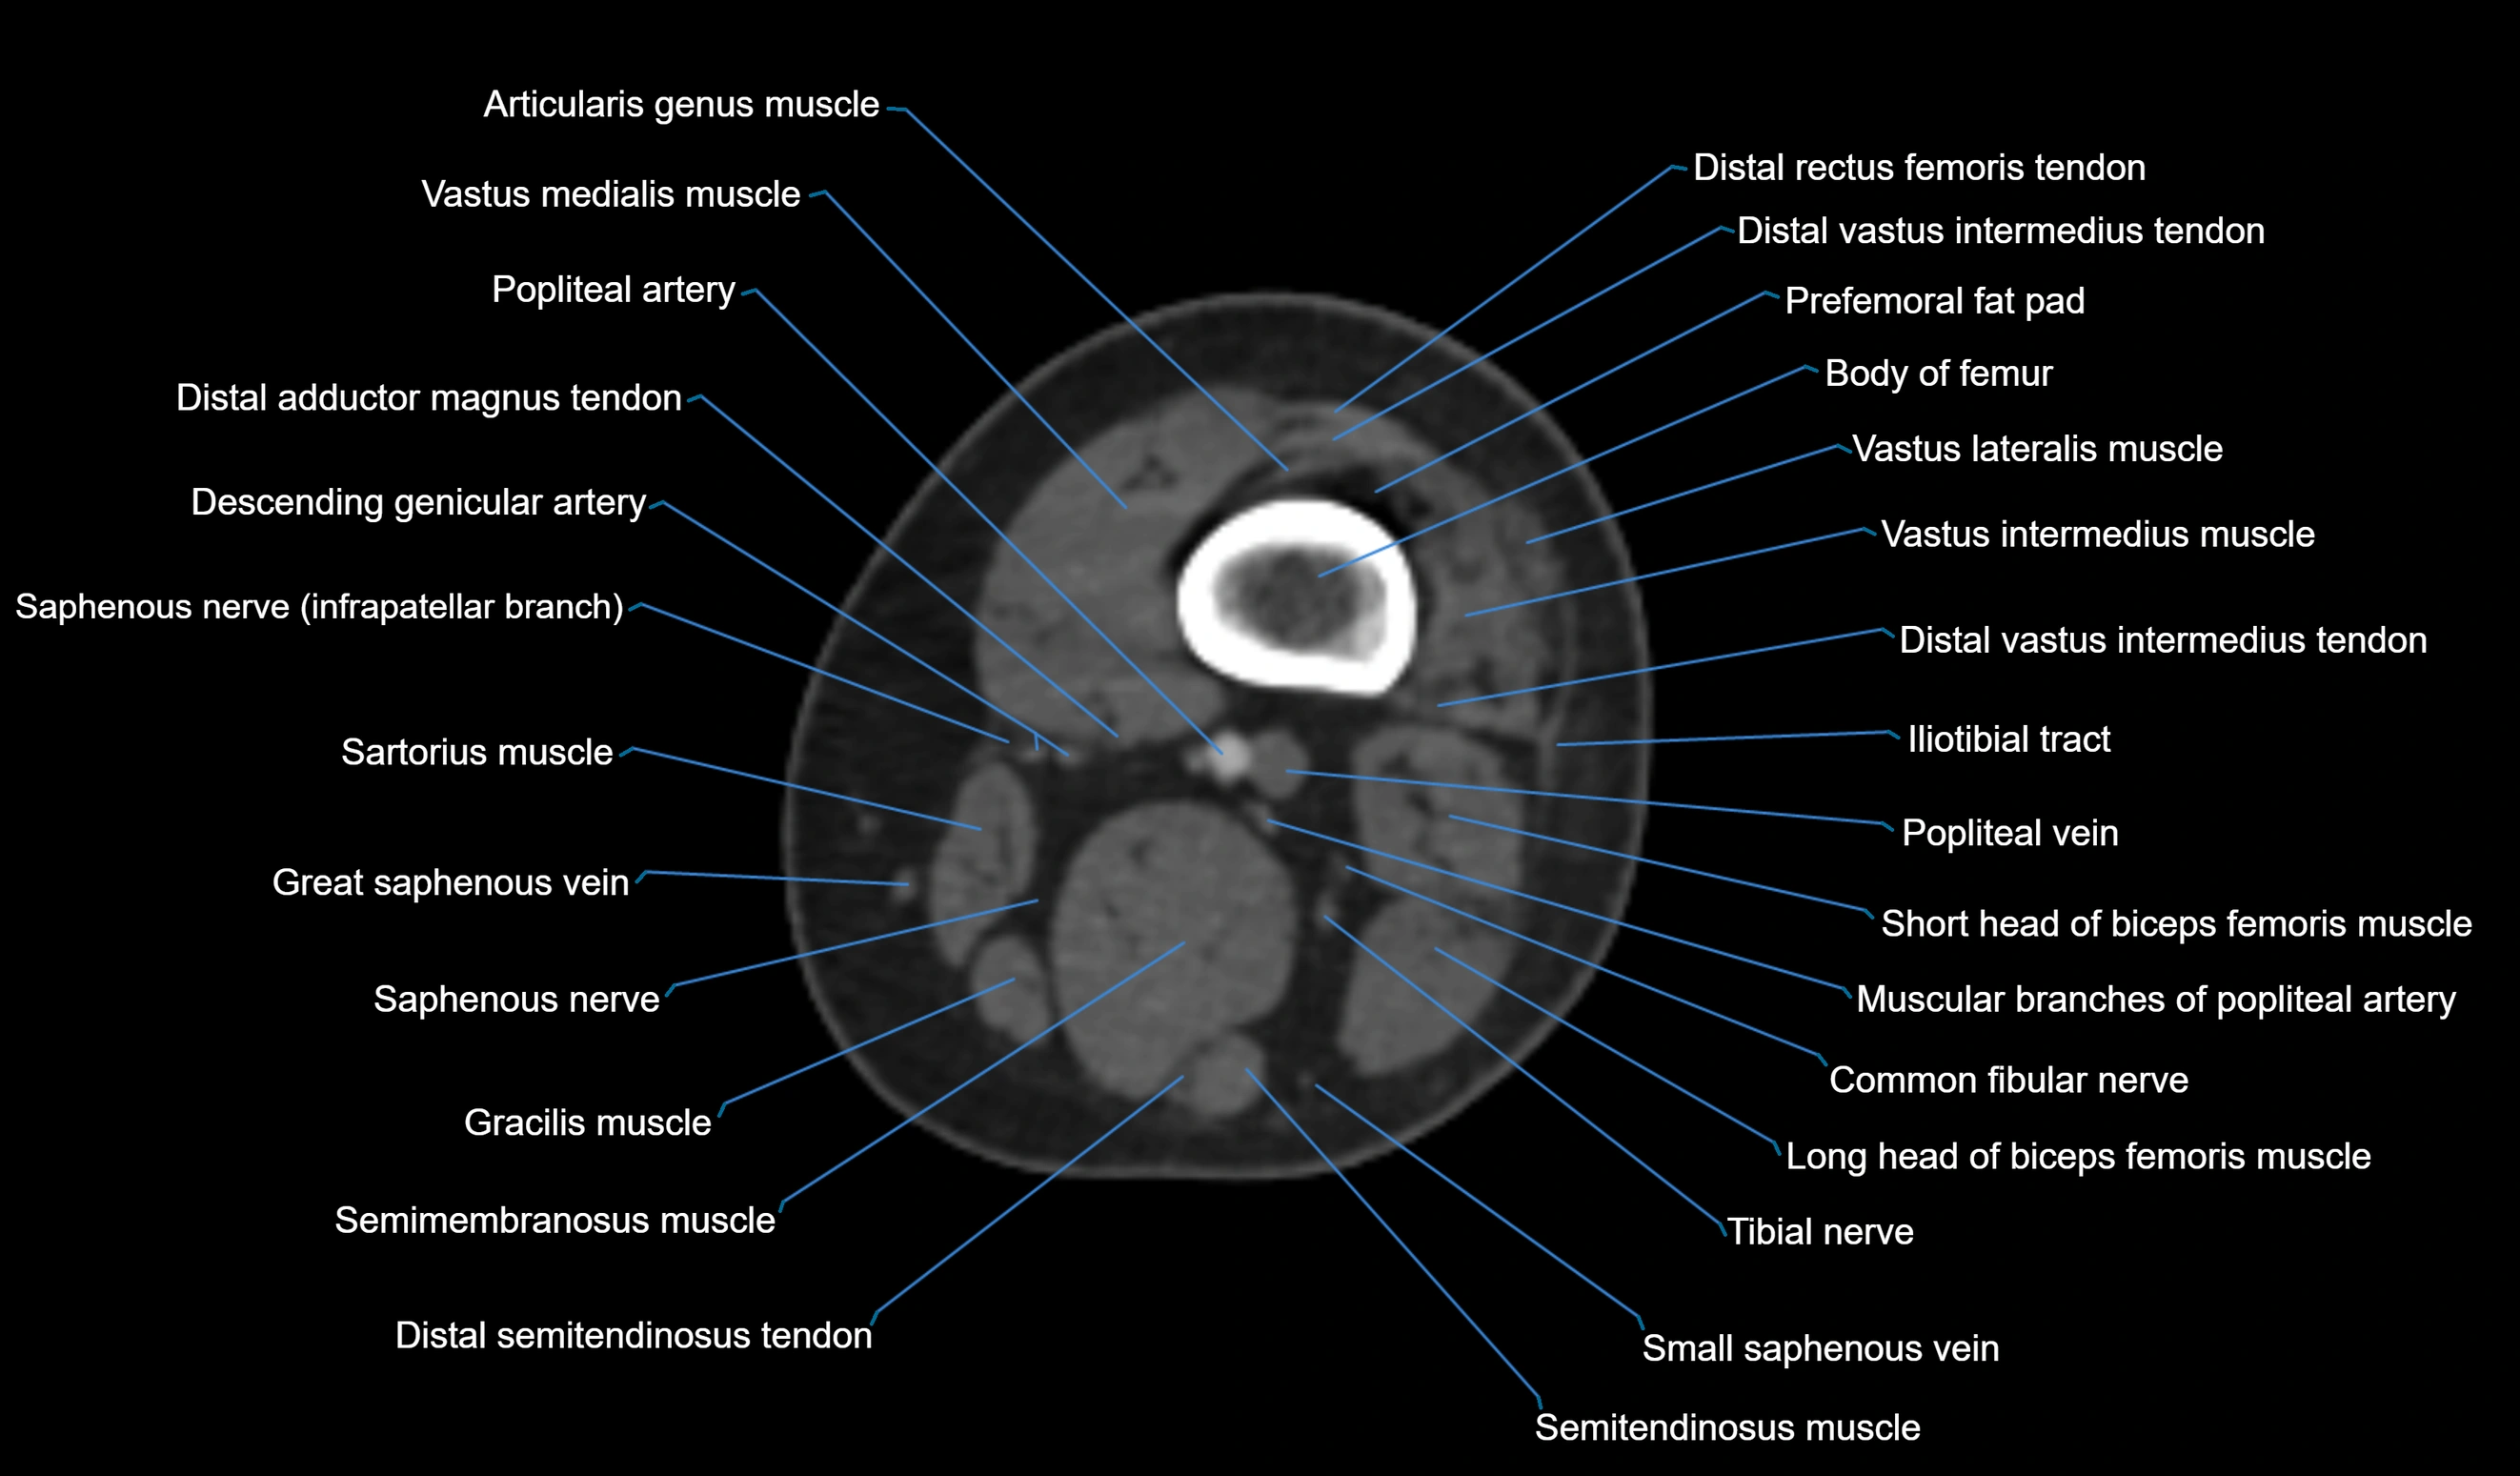

- Body of femur

- Vastus lateralis muscle

- Vastus medialis muscle

- Distal rectus femoris tendon

- Distal vastus intermedius tendon

- Prefemoral fat pad

- Tensor fasciae latae muscle

- Biceps femoris muscle (Short head)

- Biceps femoris muscle (Long head)

- Common fibular nerve

- Popliteal vein

- Popliteal artery

- Sartorius muscle

- great saphenous vein

- Saphenous nerve

- Gracilis Tendon (Proximal)

- Semimembranosus muscle

- Semitendinosus muscle

- Small saphenous vein

- Distal adductor magnus tendon

- Plantaris muscle